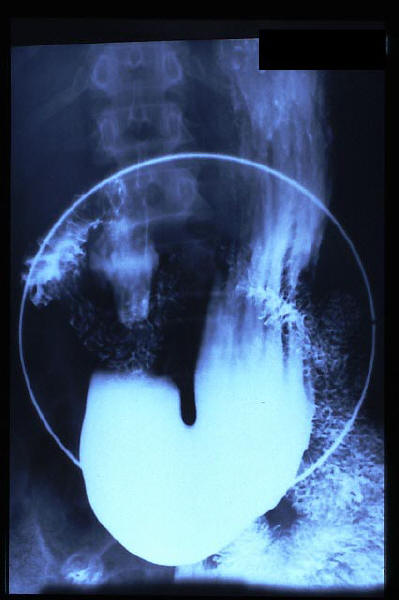

Hernia de hiato gigante.

Hernia de hiato por deslizamiento al TGED.

Hernia de hiato por deslizamiento al TEGD.

|

Hernia de hiato, nivel HA

Hernia de hiato